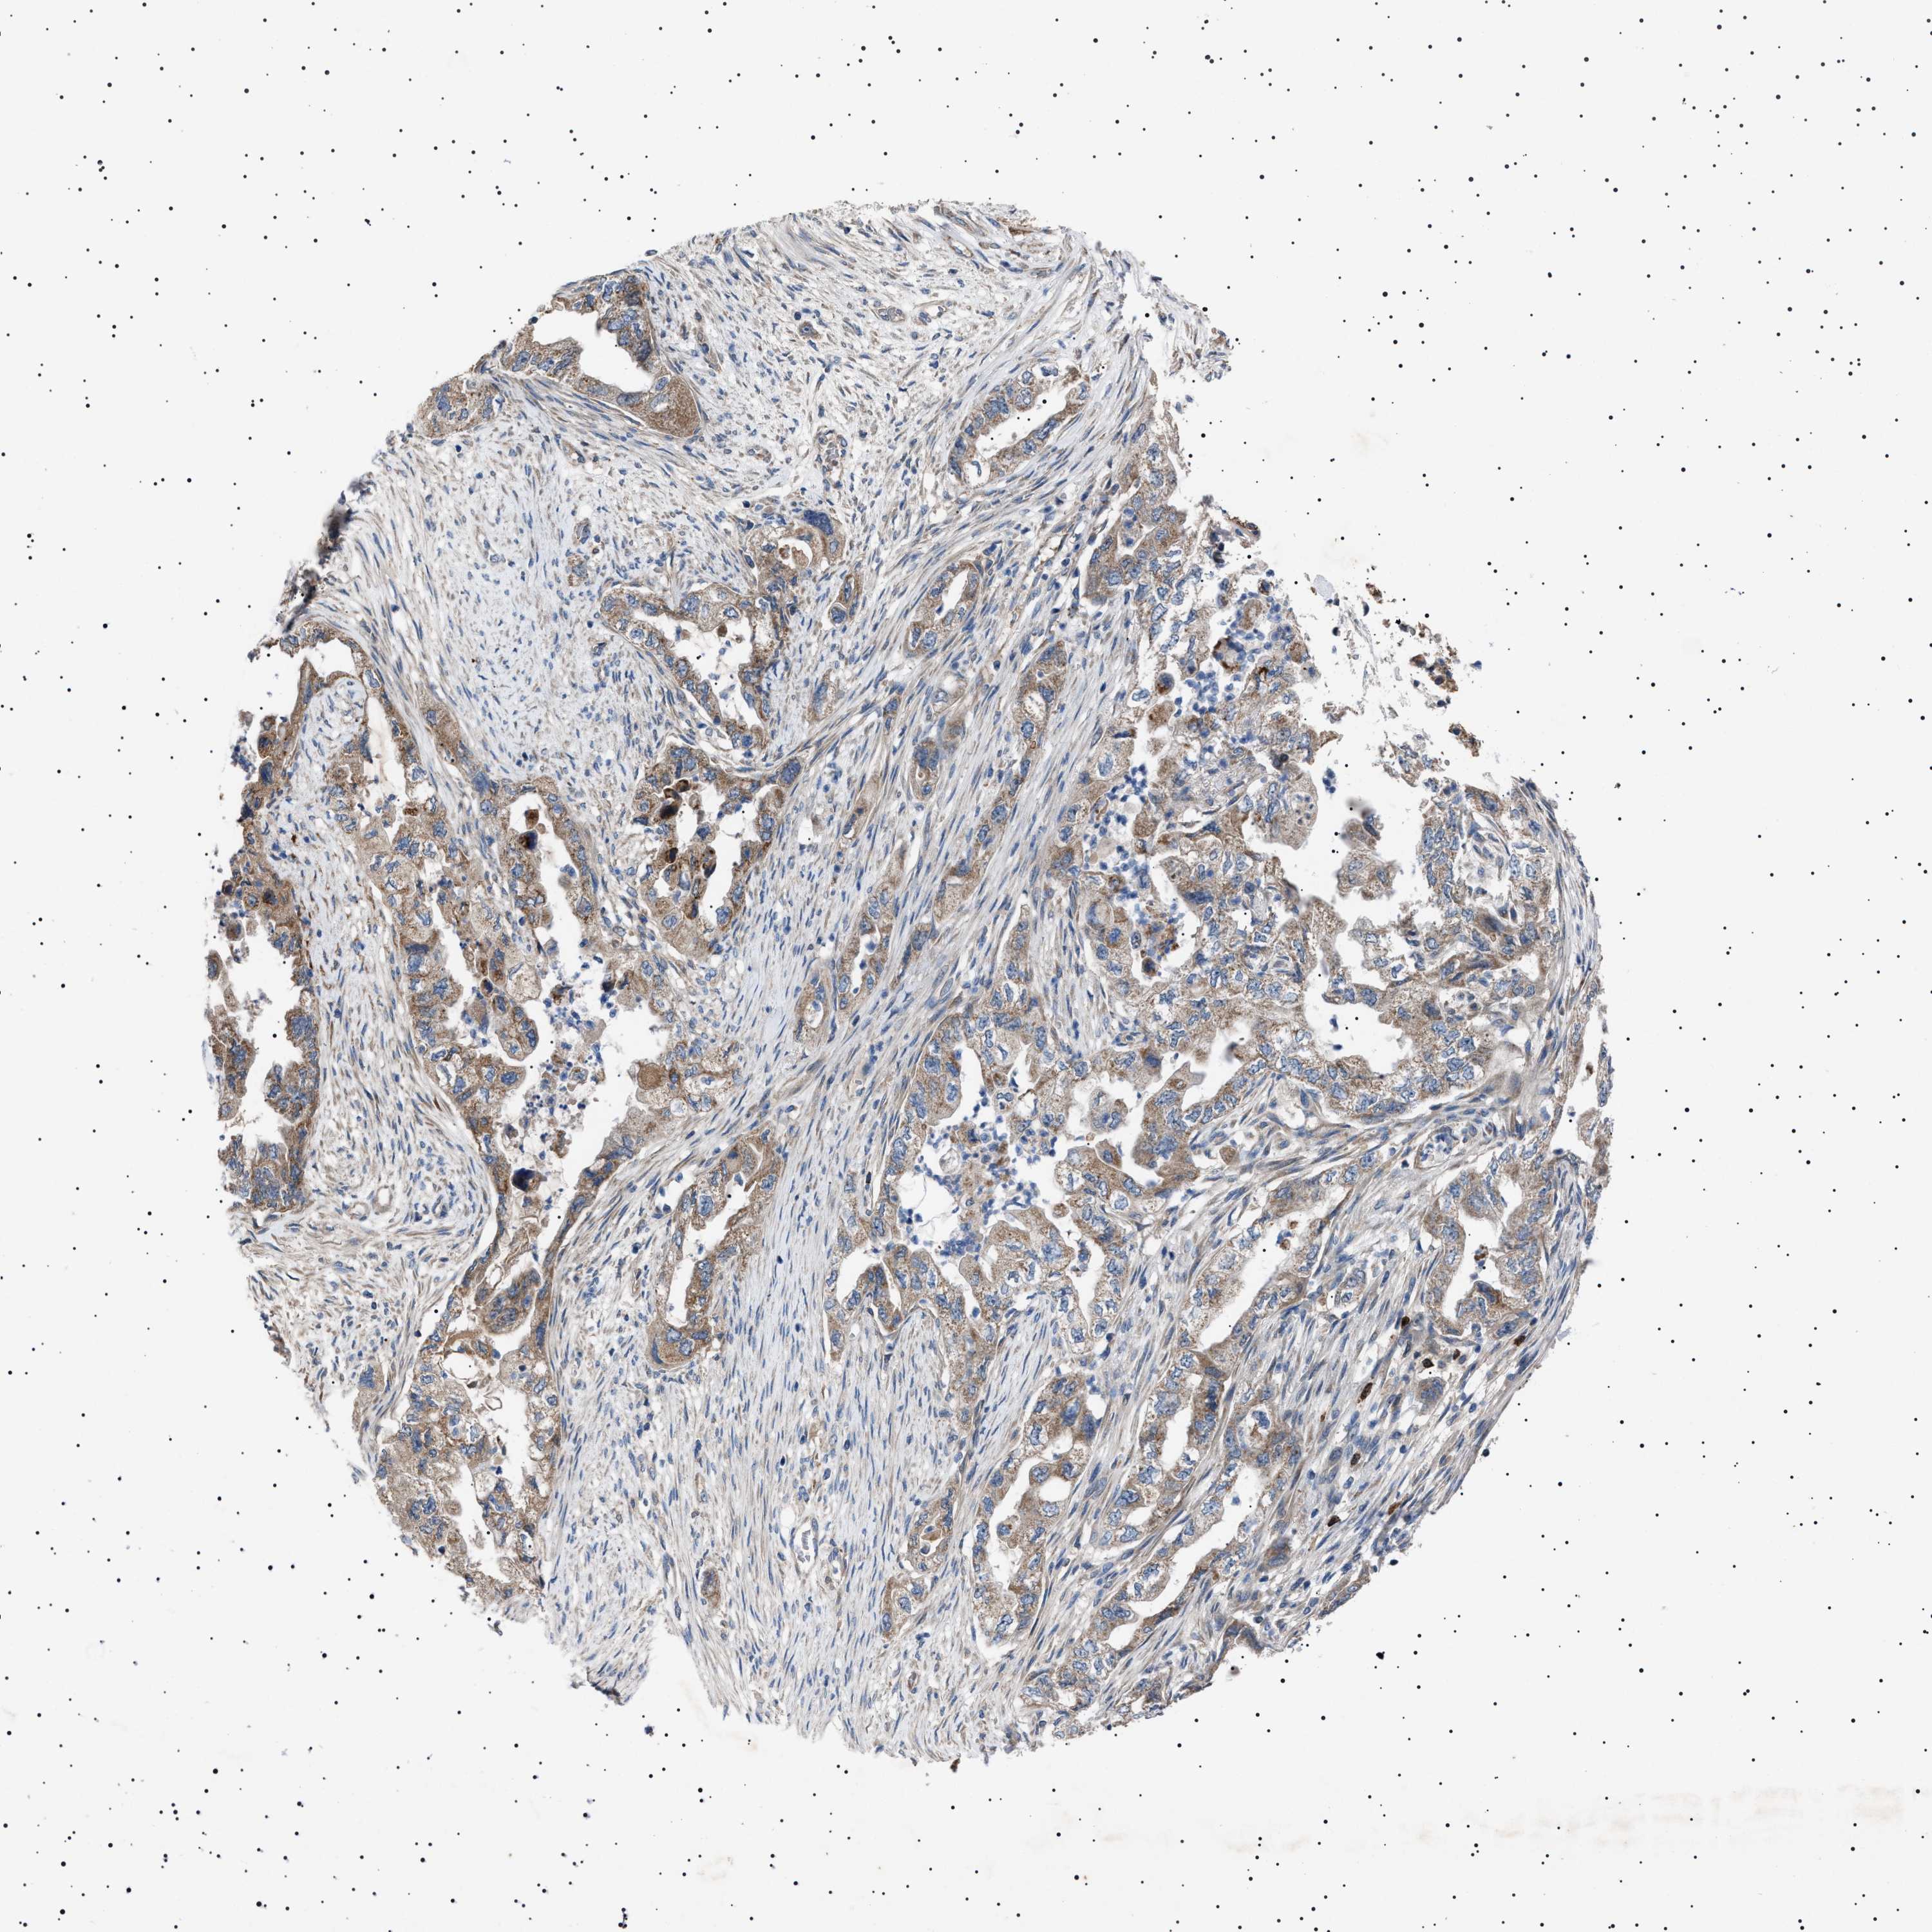

PANCREATIC CANCER - Protein expressioni

A mouse-over function shows sample information and annotation data. Click on an image to view it in a full screen mode. Samples can be filtered based on level of antibody staining by selecting one or several of the following categories: high, medium, low and not detected. The assay and annotation is described here.

Note that samples used for immunohistochemistry by the Human Protein Atlas do not correspond to samples in the TCGA dataset.

Antibody stainingi

Antibody staining in the annotated cell types in the current human tissue is reported as not detected, low, medium, or high, based on conventional immunohistochemistry profiling in selected tissues. This score is based on the combination of the staining intensity and fraction of stained cells.

Each image is clickable and will lead to virtual microscopy that enables deeper exploration of all samples and also displays staining intensity scores, fraction scores and subcellular localization as well as patient and tissue information for each sample.

Antibody HPA021223

Staining

High

Medium

Low

Not detected

Intensity

Strong

Moderate

Weak

Negative

Quantity

>75%

75%-25%

<25%

None

Location

Nuclear

Cytoplasmic/membranous

Cytoplasmic/membranous,nuclear

Adenocarcinoma, NOS